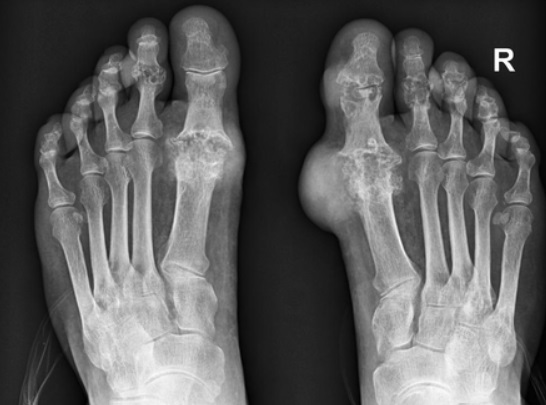

통풍이란 질병은 몸 속 요산이라는 물질이 쌓이면서 그 요산이 우리 몸에서 염증 반응을 일으켜 몸에서 관절염과 심한 통증, 또 콩팥이 망가지는 질환이자 자가 염증질환으로 알려져 있으며 주로 발가락, 발등과 같은 관절에 나타나 통풍이 생긴 경우 다리를 절단하고 싶을 정도로 아주 극심한 통증을 유발하는데 더 무서운 점은 치료시기를 놓치면 말기신부전, 뇌졸중, 심근경색 등 생명을 위협할 수 있는 합병증을 유발합니다.

통풍 증상은 그 시기에 따라 고요산혈증, 급성 통풍성 관절염, 간헐기 통풍 등 3가지 단계로 나눌 수 있으며 전형적 증상은 갑자기 엄지발가락 부위가 조금 뻐끈하다는 느낌으로 시작하며 이 부위가 급격히 붓고 통증이 심해지면 관절 주변 피부가 일어나면 열감이 느껴지고 종국에는 신발을 신을 수 없을 정도로 극심한 통증을 겪게 됩니다.

급성 통풍성 관절염은 한 개 관절에서만 나타나는데 아무래도 그 부위는 엄지발가락에서 나타나며 발 관절인 발등, 발목, 무릎 그리고 나아가서는 손목에서도 나타납니다. 통풍이 발현하면 10일 정도 지속되는데 완화가 되더라도 재발 및 악화되는 경우가 있어 치료를 받아야 합니다. 간헐기 통풍은 일반적으로 6개월에서 2년 사이 두 번째 발작이 나타나는데 통풍 발작은 치료를 받지 않으면 그 가능성이 높아져 시간이 지나면 여러 관절들로 퍼질 수 있어 반드시 치료를 받아야 하며 평상시 요산 수치를 조절해야 합니다.